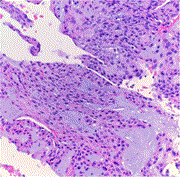

Lipoma-like hibernoma: a rare soft tissue tumor—a case series and review of the literature

Abanoub Gabra and others

Journal of Surgical Case Reports, Volume 2023, Issue 5, May 2023, rjad309, https://doi.org/10.1093/jscr/rjad309